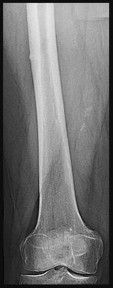

Question 10:

A 45-year-old male sustains a high-energy Schatzker IV tibial plateau fracture. Given the classic displacement pattern of this specific injury, which of the following is the most appropriate surgical approach and fixation strategy to properly neutralize the deforming forces?

Correct Answer: Posteromedial approach with a medial buttress (anti-glide) plate

A Schatzker IV fracture involves the medial tibial plateau and is typically the result of high-energy varus forces, often combined with an axial load. The primary deforming force drives the medial fragment into varus and posterior subluxation. The biomechanically sound treatment requires a posteromedial approach with a medial buttress (or anti-glide) plate to physically resist the varus and posterior displacement.